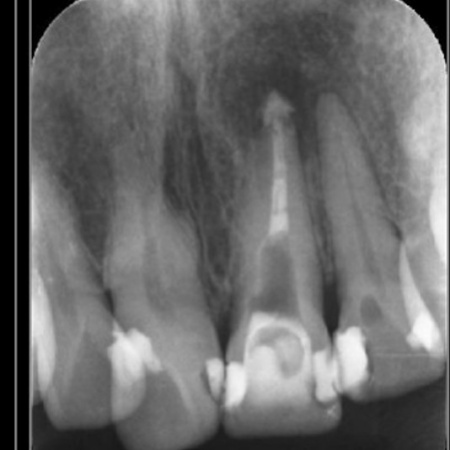

60代女性 前歯の歯茎が腫れて膿が出ている部位に精密根管治療を行った症例

拝見したところ、左上前歯の歯茎には、膿が溜まったときにできる小さな出口「フィステル」が認められました。

これは、歯根の先にできた炎症や膿の袋「根尖病巣(こんせんびょうそう)」が原因で起こります。

左上前歯は、以前、細菌感染した神経を取り除いてから薬を詰める根管治療が行われていましたが、治療後も細菌が残り、膿が溜まっている状態です。

このまま放置すると、炎症が広がって周囲の骨が溶けてしまうリスクがあるため、再度根管治療を行う必要があると診断しました。